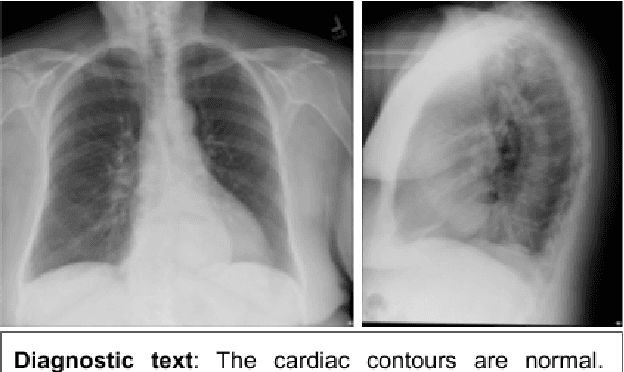

Abstract:A language model can be used to predict the next word during authoring, to correct spelling or to accelerate writing (e.g., in sms or emails). Language models, however, have only been applied in a very small scale to assist physicians during authoring (e.g., discharge summaries or radiology reports). But along with the assistance to the physician, computer-based systems which expedite the patient's exit also assist in decreasing the hospital infections. We employed statistical and neural language modeling to predict the next word of a clinical text and assess all the models in terms of accuracy and keystroke discount in two datasets with radiology reports. We show that a neural language model can achieve as high as 51.3% accuracy in radiology reports (one out of two words predicted correctly). We also show that even when the models are employed only for frequent words, the physician can save valuable time.

Abstract:This paper introduces RTEx, a novel methodology for a) ranking radiography exams based on their probability to contain an abnormality, b) generating abnormality tags for abnormal exams, and c) providing a diagnostic explanation in natural language for each abnormal exam. The task of ranking radiography exams is an important first step for practitioners who want to identify and prioritize those radiography exams that are more likely to contain abnormalities, for example, to avoid mistakes due to tiredness or to manage heavy workload (e.g., during a pandemic). We used two publicly available datasets to assess our methodology and demonstrate that for the task of ranking it outperforms its competitors in terms of NDCG@k. For each abnormal radiography exam RTEx generates a set of abnormality tags alongside an explanatory diagnostic text to explain the tags and guide the medical expert. Our tagging component outperforms two strong competitor methods in terms of F1. Moreover, the diagnostic captioning component of RTEx, which exploits the already extracted tags to constrain the captioning process, outperforms all competitors with respect to clinical precision and recall.